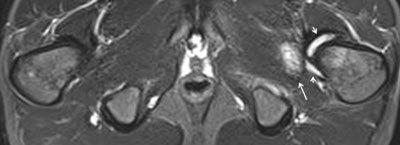

骶髂关节MRI在青少年脊柱关节炎中的诊断价值

随着可用于治疗炎症和延缓疾病进展的新医疗选择不断出现,脊柱关节炎(SpA)的早期诊断变得愈发重要。越来越多地,骶髂关节的磁共振成像(MRI)被用于早期检测炎症变化,因为它能在放射学改变明显之前很久就显示出骶髂关节炎的活动性炎症和结构性病变。儿童骶髂关节的MRI对于疑似幼年脊柱关节炎(JSpA)是一种有用的工具,尽管它尚未被纳入当前的儿科分类系统。识别儿童骶髂关节炎的MRI特征是一项挑战。由于大多数放射科医生不熟悉儿童骶髂关节的正常MRI表现,明确的定义是必不可少的。实际上,成人脊柱关节炎国际协会(ASAS)对骶髂关节炎的定义需要针对儿童进行一些调整。本综述提出了一个可能的针对儿童的MRI上活动性骶髂关节炎的特定定义建议。此外,不使用造影剂的MRI足以识别骨髓水肿(BME)、关节囊炎和关节后附着点炎,这些是JSpA中活动性骶髂关节炎的特征。在某些选定的病例中,当关节内高短tau反转恢复(STIR)信号是唯一发现时,钆增强图像可能有助于确认滑膜炎的存在。最后,我们发现儿童骶髂关节MRI上盆腔附着点炎与骶髂关节炎之间存在高度相关性。由于盆腔附着点炎表明存在活动性炎症,它可能在评估炎症状态中发挥作用。因此,在检查儿童骶髂关节MRI时应仔细寻找并记录。